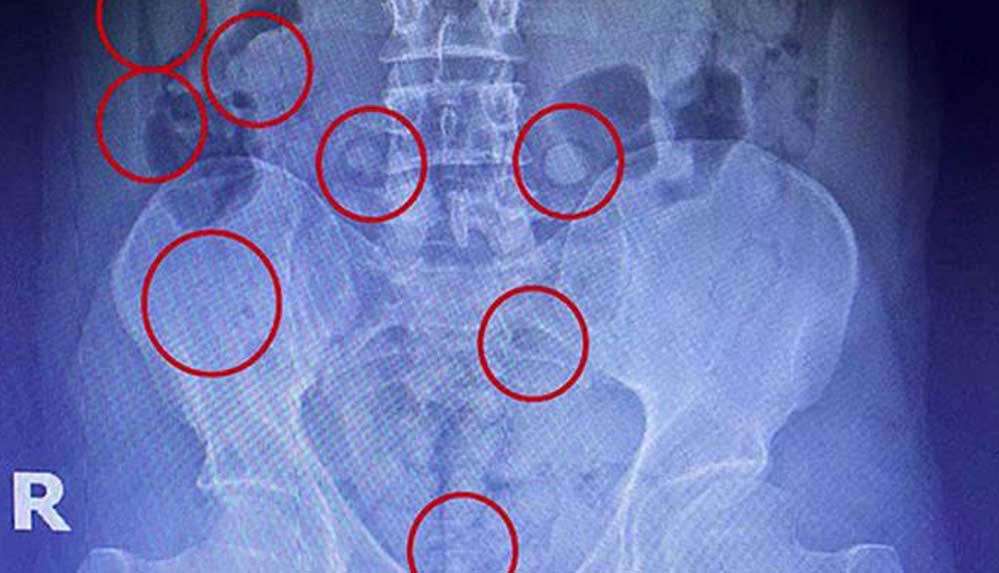

Röntgen çekimlerinde şüphelinin mide ve bağırsaklarında yabancı cisimler olduğu tespit edildi. Zanlının midesinden 45 adet kapsül içerisinde 305 gram, bağırsaklarından ise 54 kapsül halinde 400 gram metamfetamin maddesi çıkarıldı.